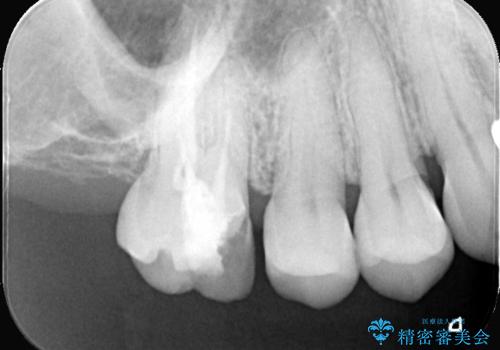

- 「奥歯の詰め物が取れた」という主訴でご来院されました。レントゲンおよび視診の結果、詰め物が外れた内部で虫歯が再発しており、根の先にも炎症が見られたため、再根管治療(根の再治療)が必要と診断しました。 特に上顎の大きな奥歯(第一大臼歯)は、通常の根管以外に「MB2」と呼ばれる隠れた根管が存在することが多く、これが未処置のままだと再発の原因となります。そこで、歯科用顕微鏡(マイクロスコープ)を用いて徹底的に内部を清掃し、その後、強度と審美性に優れたオールセラミッククラウンで修復する計画を立案しました。

顕微鏡によるMB2の発見: 歯科用顕微鏡(マイクロスコープ)を使用し、根管内を強拡大して観察したところ、事前の予想通り、従来の治療では見逃されていた**第4の根管「MB2」**を発見しました。この未処置だった根管内の汚れを徹底的に除去・消毒することで、痛みの再発リスクを根本から取り除きました。